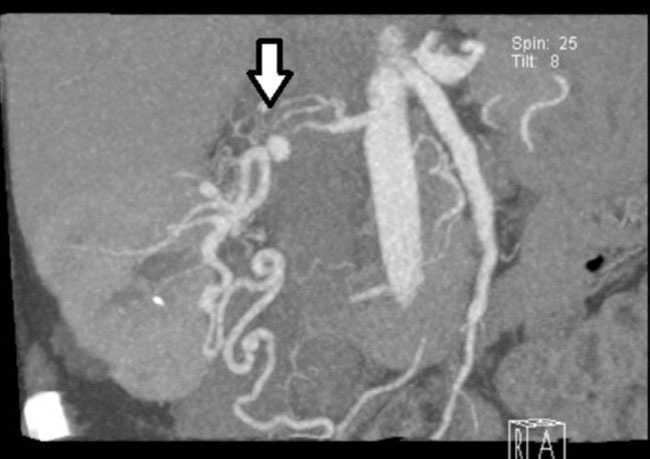

Following surgery, the blood pressure normalised and since then maintained around 120/80mmHg without drugs. In the postoperative imaging study (renal MRA) (Figure 2), normal kidney graft was observed with new vascularisation.

Figure 2. Renal magnetic resonance angiography